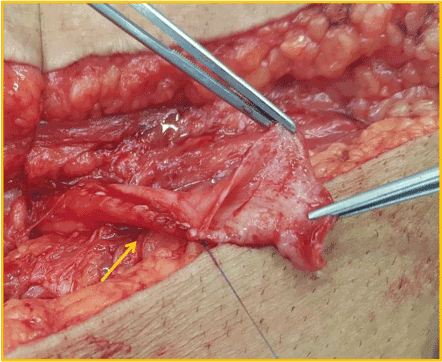

Although there were no other symptoms, a slow increase in serum creatinine, from 1,5mg/dL to 2,4mg/dL, was noticed in the first three post-operative years. Physical examination found a right sided inguinal hernia. Abdominal ultrasound revealed a severe hydronephrosis of the transplant kidney but the ureter could not be visualized. An abdominal computed tomography (CT) showed severe ureterohydronephrosis with herniation of the ureter into the inguinal canal (Figure 1), prompting surgical exploration. Through the previous right-side Gibson incision, the spermatic funiculi and hernial sac were identified and isolated. Exploration of the herniary sac revealed a long ureter, with a dilated proximal portion (3cm wide), followed by an abrupt transition to a rather typical distal segment, close to the bladder wall (Figure 2). Both segments appeared well vascularized and viable. Given these findings and the excessive length of the ureter, ureterectomy of the distal segment followed by a tailored ureteroplasty (Figure 3) and new Lich-Gregoir ureteroneocystostomy of the proximal segment over a double J stent was performed. The posterior wall defect was mended through Lichtenstein technique. A bladder catheter was kept for one week and the ureteral stent for one month. After the removal of the bladder catheter, ultrasound and CT scan were unremarkable (Figure 4) and serum creatinine decreased from 2.4mg/dL to 2.05mg/dL. Patient is still in follow-up, without any sign of recurrence.

Figure 2. Blue arrow: proximal dilated portion of the transplant´s ureter; yellow arrow: point of strangulation at the distal portion of the ureter